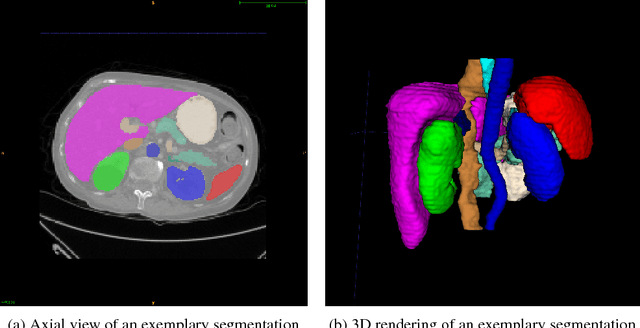

Abstract:To efficiently establish training databases for machine learning methods, collaborative and crowdsourcing platforms have been investigated to collectively tackle the annotation effort. However, when this concept is ported to the medical imaging domain, reading expertise will have a direct impact on the annotation accuracy. In this study, we examine the impact of expertise and the amount of available annotations on the accuracy outcome of a liver segmentation problem in an abdominal computed tomography (CT) image database. In controlled experiments, we study this impact for different types of weak annotations. To address the decrease in accuracy associated with lower expertise, we propose a method for outlier correction making use of a weakly labelled atlas. Using this approach, we demonstrate that weak annotations subject to high error rates can achieve a similarly high accuracy as state-of-the-art multi-atlas segmentation approaches relying on a large amount of expert manual segmentations. Annotations of this nature can realistically be obtained from a non-expert crowd and can potentially enable crowdsourcing of weak annotation tasks for medical image analysis.